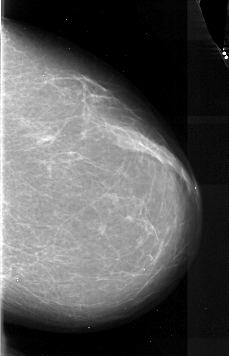

A_1083_1.RIGHT_MLO

RIGHT_MLO LINES 5941 PIXELS_PER_LINE 3061 BITS_PER_PIXEL 16 RESOLUTION 42 NON_OVERLAY